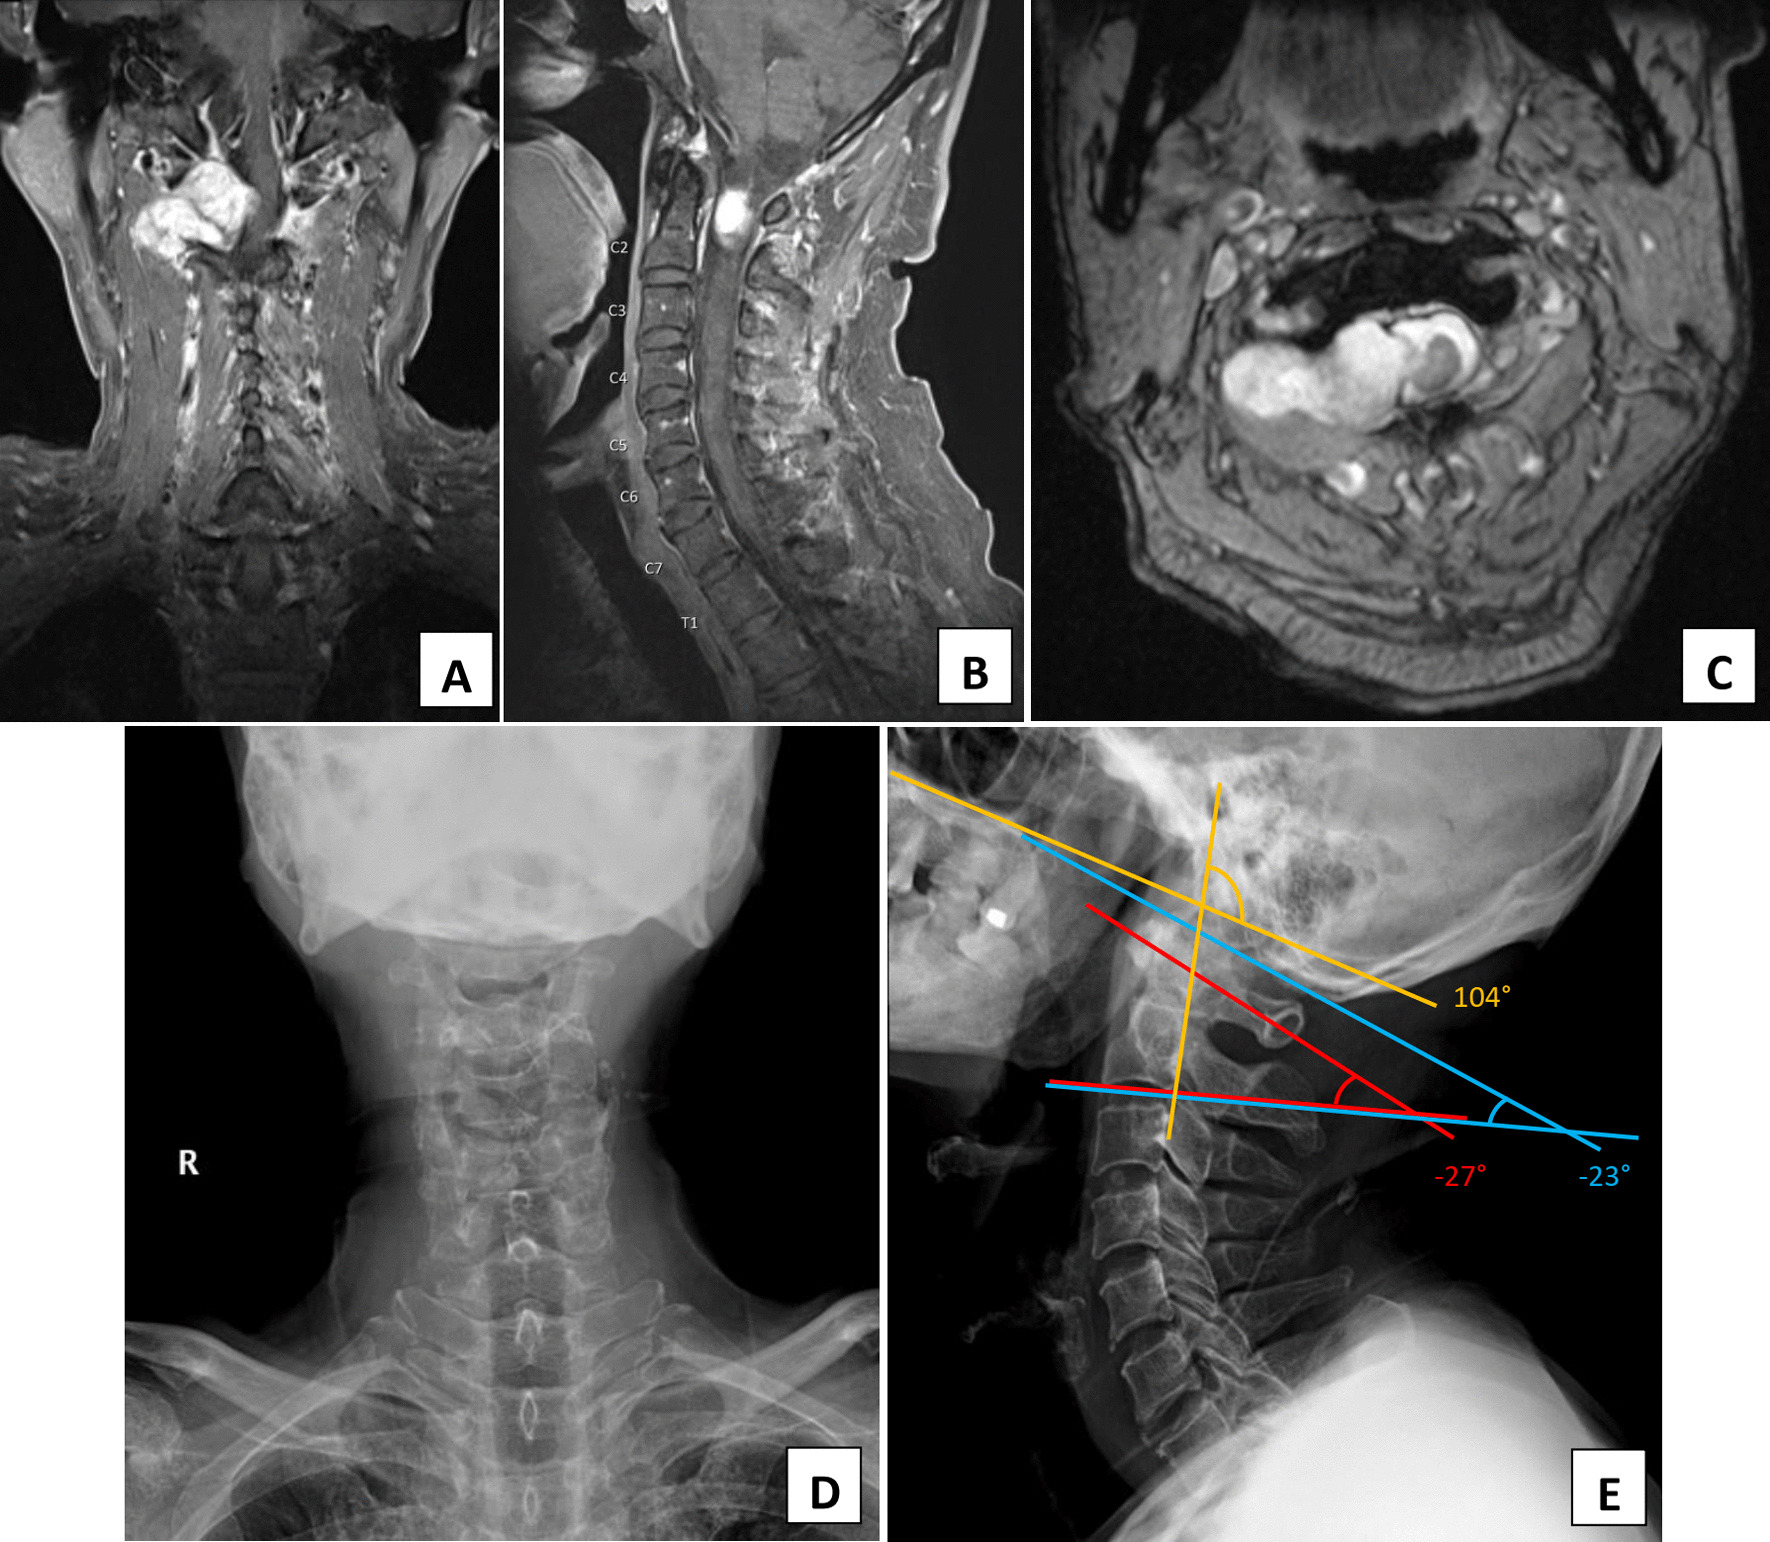

Fig. 1.

T1-weighted, post-contrast injection magnetic resonance imaging images show an enhancing lesion at an extradural location with an intradural extension at the right side of the C1/C2 vertebrae in the coronal (a), sagittal (b), and axial (c) plane. The mass effect caused corresponding spinal cord compression with left posterolateral displacement. No obvious cord signal abnormality was seen. Plain film readiographs of the preoperative cervical spine in the anteroposterior (d) and lateral view (e) also show the measured angle of occiput-C2 (blue), C1–C2 (red), and Takami’s angle (yellow) of − 23°, − 27°, and 104°, respectively

A 75-year-old Thai man with a recent history of tuberculosis infection presented with an enlarged tonsil. Following an initial physical examination, the otolaryngologistsn sent the patient for computed tomography (CT) scan of his neck, which revealed that his tonsil was normal but that there was a mass located incidentally at his cervical spine at the level of C1/C2. There was no history of neck pain, gait abnormalities, or neurological problems. Physical examination revealed only increased tendon reflex of his upper and lower extremities. His neck range of motion was full, and his bowel bladder function was normal. Neither paralysis nor paresthesia was observed. The magnetic resonance imaging (MRI) revealed an extradural enhancing mass at the right C1/C2 level compressing the spinal cord (Fig. 1). The provisional diagnosis was a benign tumor with suspicion of schwannoma. Despite the subtle clinical neurological deficit, the MRI finding of severe spinal cord compression was concerning, and treatment options were discussed. Due to the high risk of creating instability following resection of the tumor, the treatment chosen was that of additional fusion of the upper cervical spine. Preoperative plain radiographs of the cervical spine and the upper cervical sagittal alignment are shown in Fig. 1.